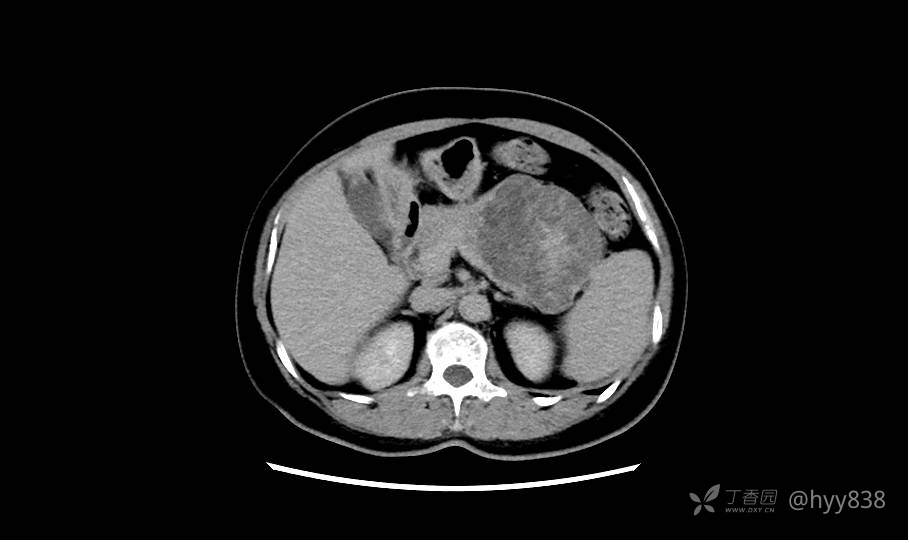

简要病史:2周前,患者无明显诱因出现剑突下不适,以隐痛为主,无明显加重、缓解因素。门诊以胰腺巨大占位收入院进一步诊治。

临床诊断:胰腺占位